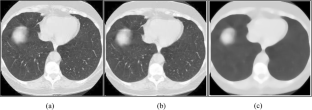

Fig. 1